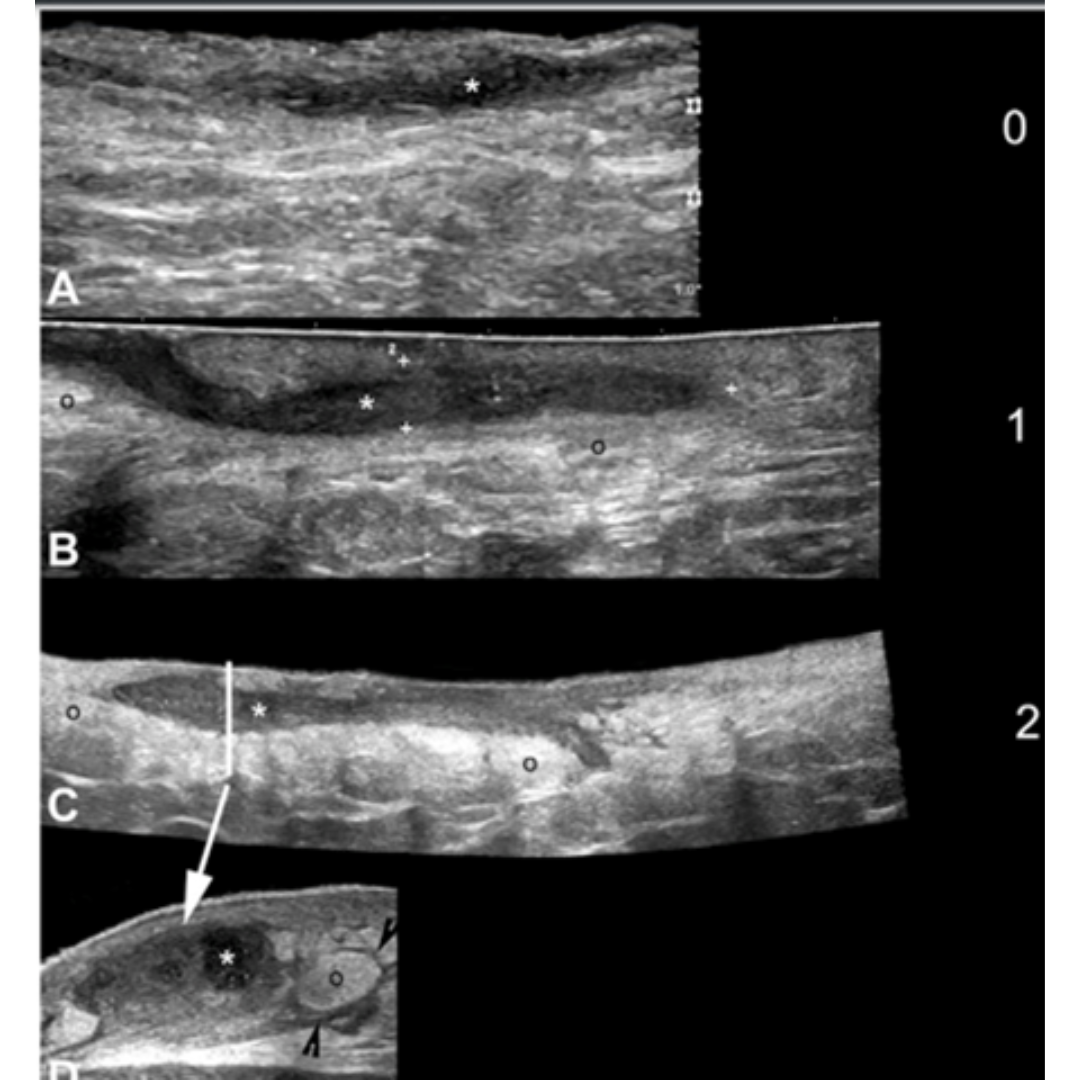

Existe además del estadio la clasificación del trayecto fistuloso descrito en la tabla 3, esta clasificación se basa en el Grado de fibrosis y edema de los trayectos fistulosos. Ecográficamente los grados de fibrosis se observan como halos rodeando las fistulas (figura 8) y el edema se observa rodeando los trayectos fistulosos como áreas hipoecogénicas en la hipodermis ejemplificados en figura 7. El grado de edema también se relaciona con la presencia de vascularización interna de la fistulas (figura 6).

Figura 7: A a D de menor a mayor edema. Se muestra la clasificación de Edema hipodérmico (o) adyacente los trayectos de folículos de HS. Se observan imágenes en modo B con campo de visión extendido demostrando el eje largo de las fistulas (*). En D una vista transversal del trayecto fistulosos (*) es mostrado con grado 2 de edema (o). Se observa liquido hipoecoico (puntas de flechas negras) entre los lóbulos grasos en D*.

Figura 9: Tipos de fístulas de tractos en HS. Clasificación tipo 3 (C) muestra el borde grueso hipoecogénico (punta de flecha), que sugiere cicatrización fibrótica en la periferia del trato fistuloso y el edema (o) del tejido graso hipodérmico en comparación con los tipos anteriores. (o) edema hipodérmico; es un marcador positivo de los bordes del trayecto fistuloso.